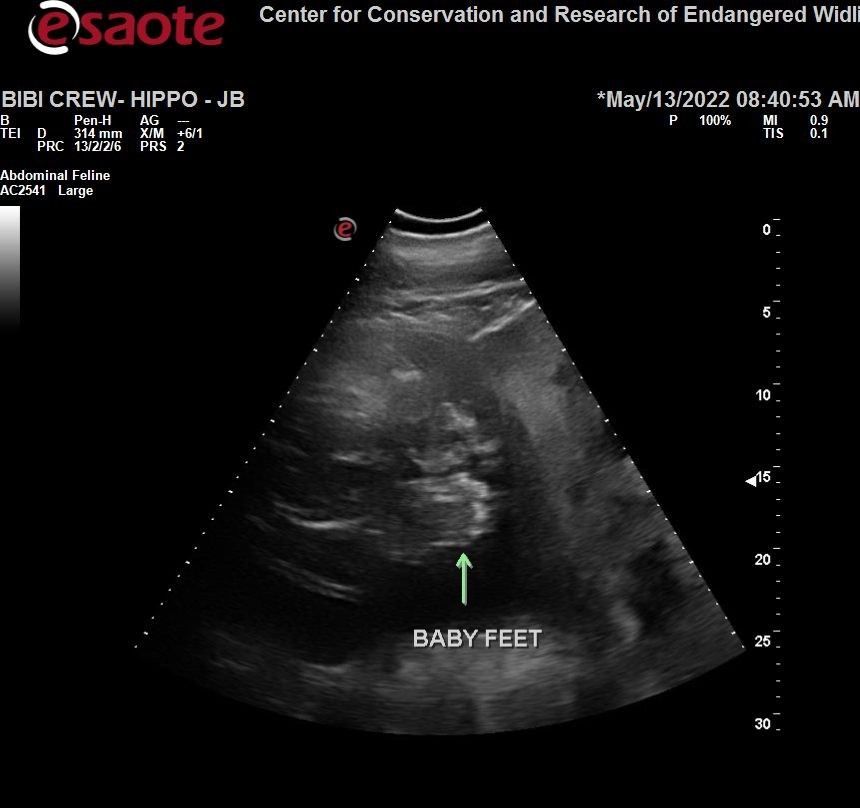

An ultrasound shows the feet of a baby hippo.

A sonogram shows the feet of a baby hippo. Photo/Cincinnati Zoo & Botanical Garden

“That’s why we try to get between the mammary glands since it has the least amount of tissue between us and the fetus,” she said. “We were able to get a pretty good view of his or her feet and get a glimpse of a heart beating.”